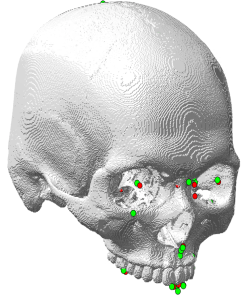

Figures 7(b) and 8(b) show the qualitative and quantitative results of the 3D CNNs. The mean 3D distance error decreased to 2.72 mm when compared to the initial detection error of 4.23 mm (Figure 6(b)). According to results shown in Table 3, the proposed method achieved an error range of 1 to 4 mm for the detection of most landmarks. In addition, as shown in Figure 10(b), the proposed method significantly reduced the mean and variance of error for the test subjects, compared to the initial detection.

Figures 7(a) and 8(a) show the final cranial landmark estimation results in qualitative and quantitative formats. The mean detection error for all cranial landmarks was 3.09 mm, which decreased from the initial estimation error of 3.68 mm (Figure 6(a)). As shown in Table 3, the error for most cranial landmarks fell within the range of 1 to 4 mm.